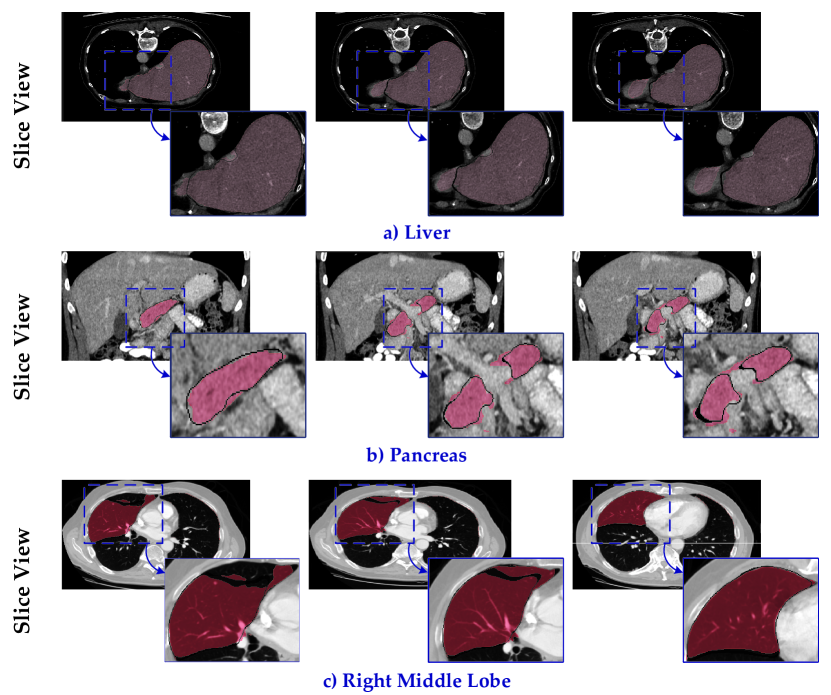

Refer to caption

Fig. 5: Examples of the refinement results on the Liver, Pancreas, and Right Middle Lobe. The dotted blue boxes highlight the same areas in the initial results, implicit refinement results, and template space. a) Structural error has been corrected according to the template. b) Staircase artifact of the boundary has been refined. c) The misclassification problem has been alleviated.

The standard 3D UNet[10] was chosen as the segmentation model. Equipped with the implicit shape modeling, the results can be refined from an average 0.407 CD / 0.113 EMD to 0.232 CD / 0.087 EMD on the Liver dataset, from 0.223 CD / 0.097 EMD to 0.128 CD / 0.069 EMD on the Pancreas dataset, and from 0.677 CD / 0.115 EMD to 0.417 CD / 0.100 EMD on the Lung Lobe dataset. To further investigate the effectiveness of the refinement brought from implicit shape modeling, we provided visualization examples of the refinement results on the Liver, Pancreas, and Right Middle Lobe in Fig.5. The dotted blue boxes highlighted the refined areas, same spatial location in the initial result, implicit refinement result, and template space. The CD and EMD were also decreased upon the implicit refinement. According to the learned template, the succeeding implicit refinement could alleviate the structural errors, staircase artifacts, and misclassification problem.

As mentioned before, we could conduct the inverse transform of PICCT of each instance to map the refinement shape surface to the volume result in the discrete space. Compared with the initial results generated by 3D UNet, the proposed implicit shape modeling refined the HD95 from 18.05 mm to 11.40 mm on the Liver dataset, from 4.91 mm to 4.13 mm on the Pancreas dataset, and from 14.97 mm to 12.04 mm on the Lung Lobe dataset. Table 3 demonstrated that the proposed method also performed better than other comparative methods, especially the surface distance based measurements HD95 and ASSD had been improved substantiality. Fig.8 provided the slices view of the comparison between the initial results and implicit refinement results. It can be observed that the under/over segment problem had been alleviated with the integration of template anatomical prior. In addition, the implicit refinement was performed in the continuous space, hence, the response near the boundary became more consistent, manifested as smoother.